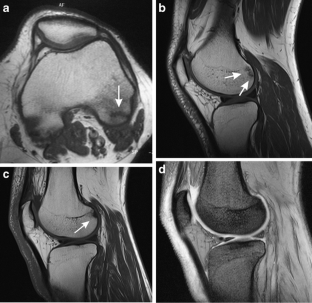

Subchondral impaction fractures of the non-weight-bearing portion of the lateral femoral condyle

Sixteen cases of intra-articular impaction fractures in a posterior, non-weight-bearing area of the lateral femoral condyle were diagnosed in patients with a mean age of 40. Eight were associated with recreational sports activities and 4 with repeated kneeling. There were no fractures documented in the non-weight-bearing aspect of the medial femoral condyles. Proposed underlying mechanisms for development of this type of fracture are presented.

Awareness, along with a high level of suspicion, that non-specific knee pain, especially in patients involved in athletic activities, could be due to intra-articular impaction fractures of the non-weight-bearing posterior aspect of the lateral femoral condyle is essential and MRI is the mainstay of diagnosis.

Fig. 2